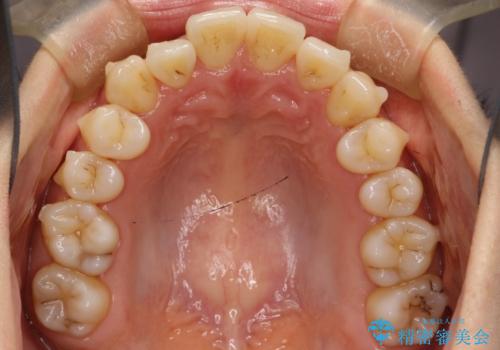

前歯が前後反対にかんでいる インビザラインによる目立たない矯正

- 前歯のかみ合わせを主訴に来院されました。

なるべく目立たずに矯正をしたいとのことで、インビザラインで矯正をすることとしました。

歯と歯の間をわずかに削り、ガタガタを改善しました。